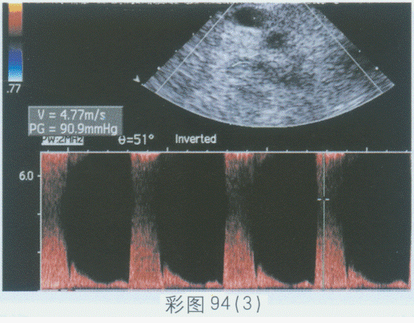

198、单项选择题

临床资料:男,67岁,自述反复头晕2年余,加重2天,发作性晕厥,上肢麻木。既往史:脑梗塞3年。临床物理检查:颈部有血管杂音。超声综合描述:胸骨上窝扫查右锁骨下动脉起始段管腔内透声不清亮,可见中等回声(箭头所示),CDFI:局部血流信号充盈缺损,PW:V4.77m/s。CDFI:右椎动脉血流出现红、蓝交替现象;PW:右椎动脉血流频谱收缩期呈反向血流,舒张期呈正向血流。见彩图94。

超声提示()。

A.锁骨下动脉窃血综合征(右锁骨下动脉起始段动脉硬化斑块形成并重度狭窄,同侧右侧椎动脉血流逆行流入右锁骨下动脉)

B.右椎动脉狭窄

C.右椎动脉闭塞

D.右椎动脉正常声像图